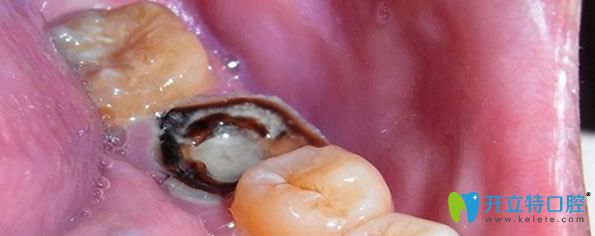

牙髓炎是一種嚴(yán)重的制病因素,一旦發(fā)炎不能好轉(zhuǎn),不是吃了消炎藥就可以恢復(fù),牙髓炎持續(xù)惡化,繼續(xù)發(fā)展就會(huì)造成牙髓死亡。牙齒沒(méi)有得到及時(shí)的診治,久而久之,牙齦就會(huì)萎縮,牙齒就會(huì)變得稀疏松動(dòng),導(dǎo)致牙齒脫落。

急性牙髓炎不治療的后果